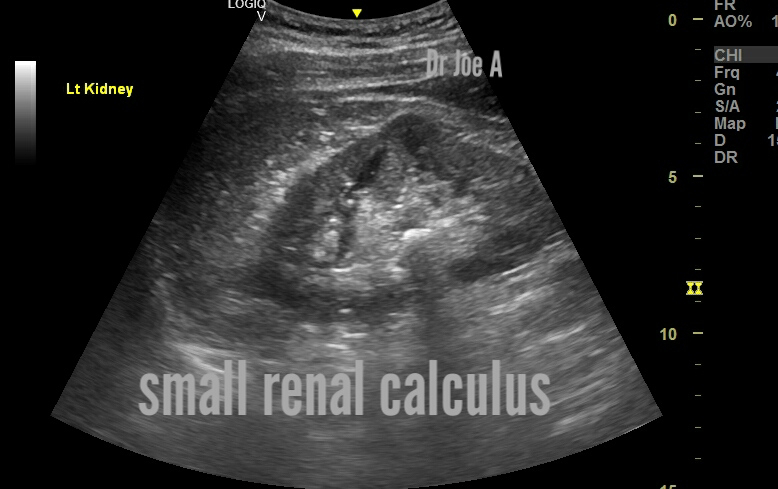

This calculus is huge, is it a staghorn?

Staghorn calculus is a large branching kidney stone that can partially or completely fill the pelvicalyceal complex (CHLC) of the kidney.